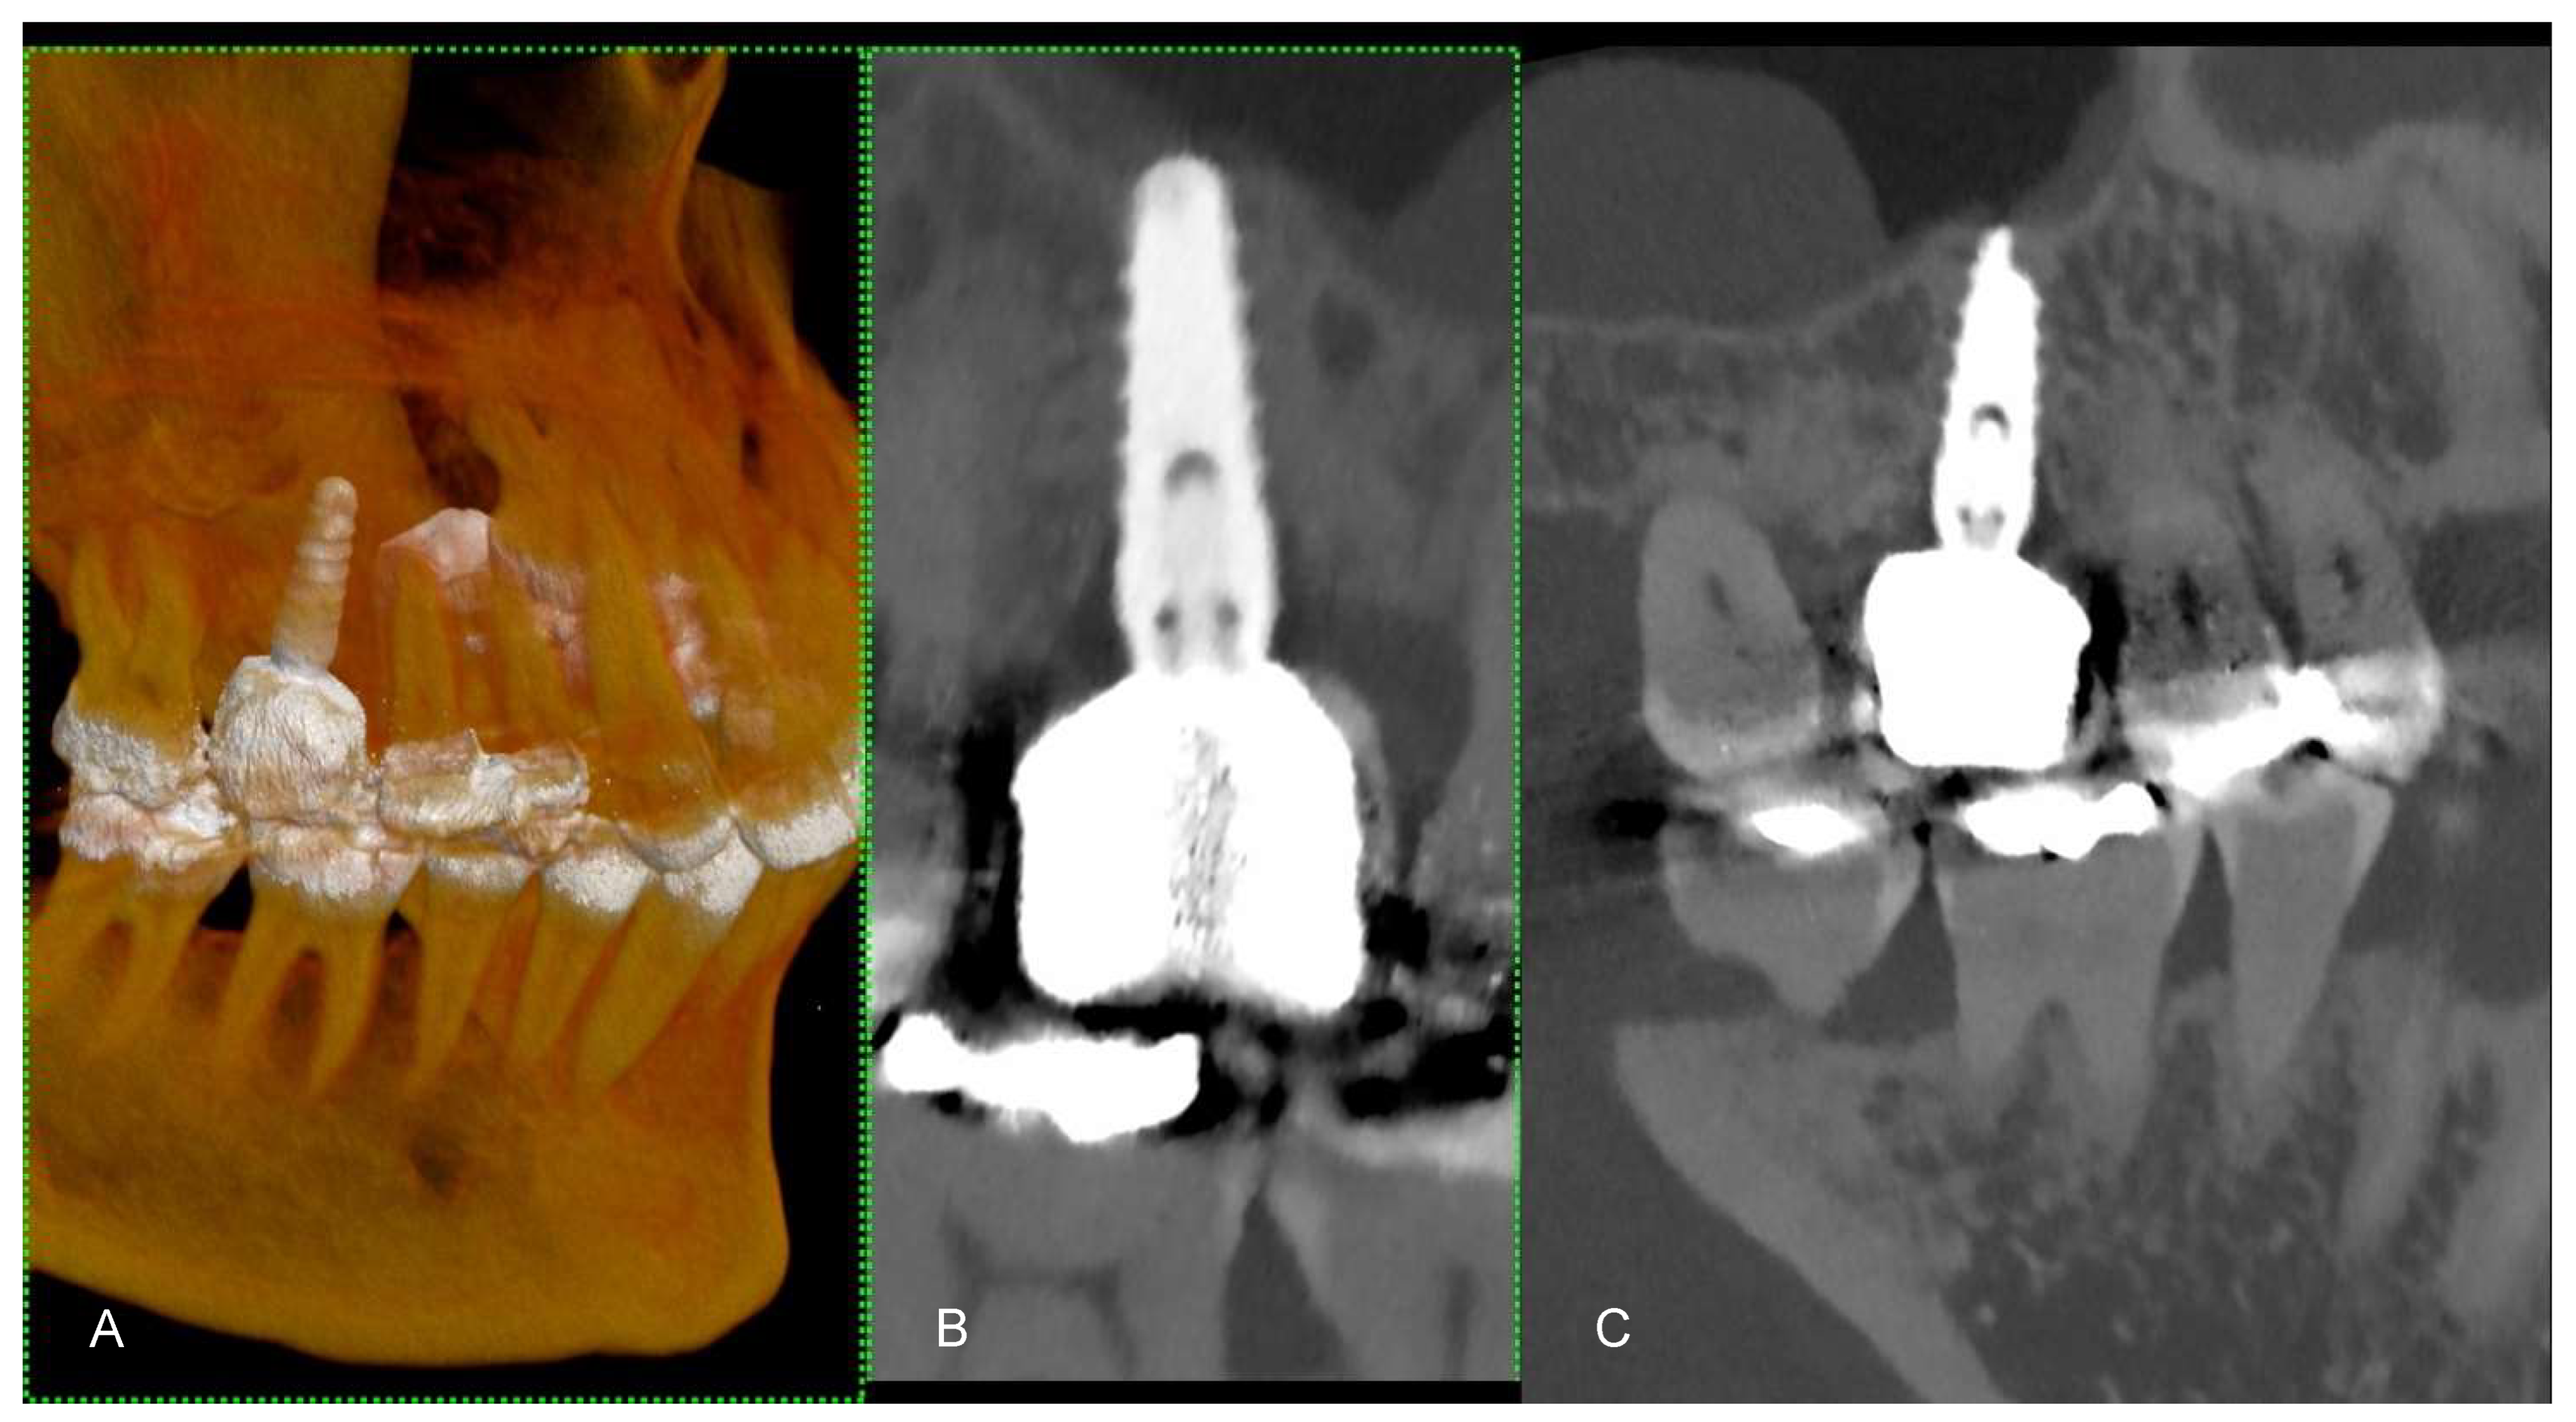

Figure 5. (A) The figure shows a 3D cinematic rendering of dental implants. This type of visualization helps to ensure that the implants are properly positioned for the best functional and aesthetic outcomes. (B) The 2D cross-sectional image of a single dental implant in the jawbone. This type of image is useful for evaluating the quality and density of the bone surrounding the implant and ensuring that the implant is properly placed. (C) This is another cross-sectional study, which also shows the detailed interaction between the implants and the bone, ensuring that the implants are not encroaching upon any anatomical structures, such as nerves or sinuses, and that there is enough bone around the implants for a stable fit. The scan was performed on a commercial whole-body Dual Source Photon Counting CT scanner (NAEOTOM Alpha, Siemens Healthineers); 0.2 mm slice thickness, 0.1 mm reconstruction increment, FOV 140 mm, spiral acquisition with tube current modulation; resolution matrix of 1024 × 1024 pixels on the source axial reconstructions VIM at 190 KeV. The actual displayed resolution is 0.1 mm (100 microns). Abbreviations: 3D, Three-Dimensional; VMI = Virtual Monoenergetic Imaging; FOV = Field of View.